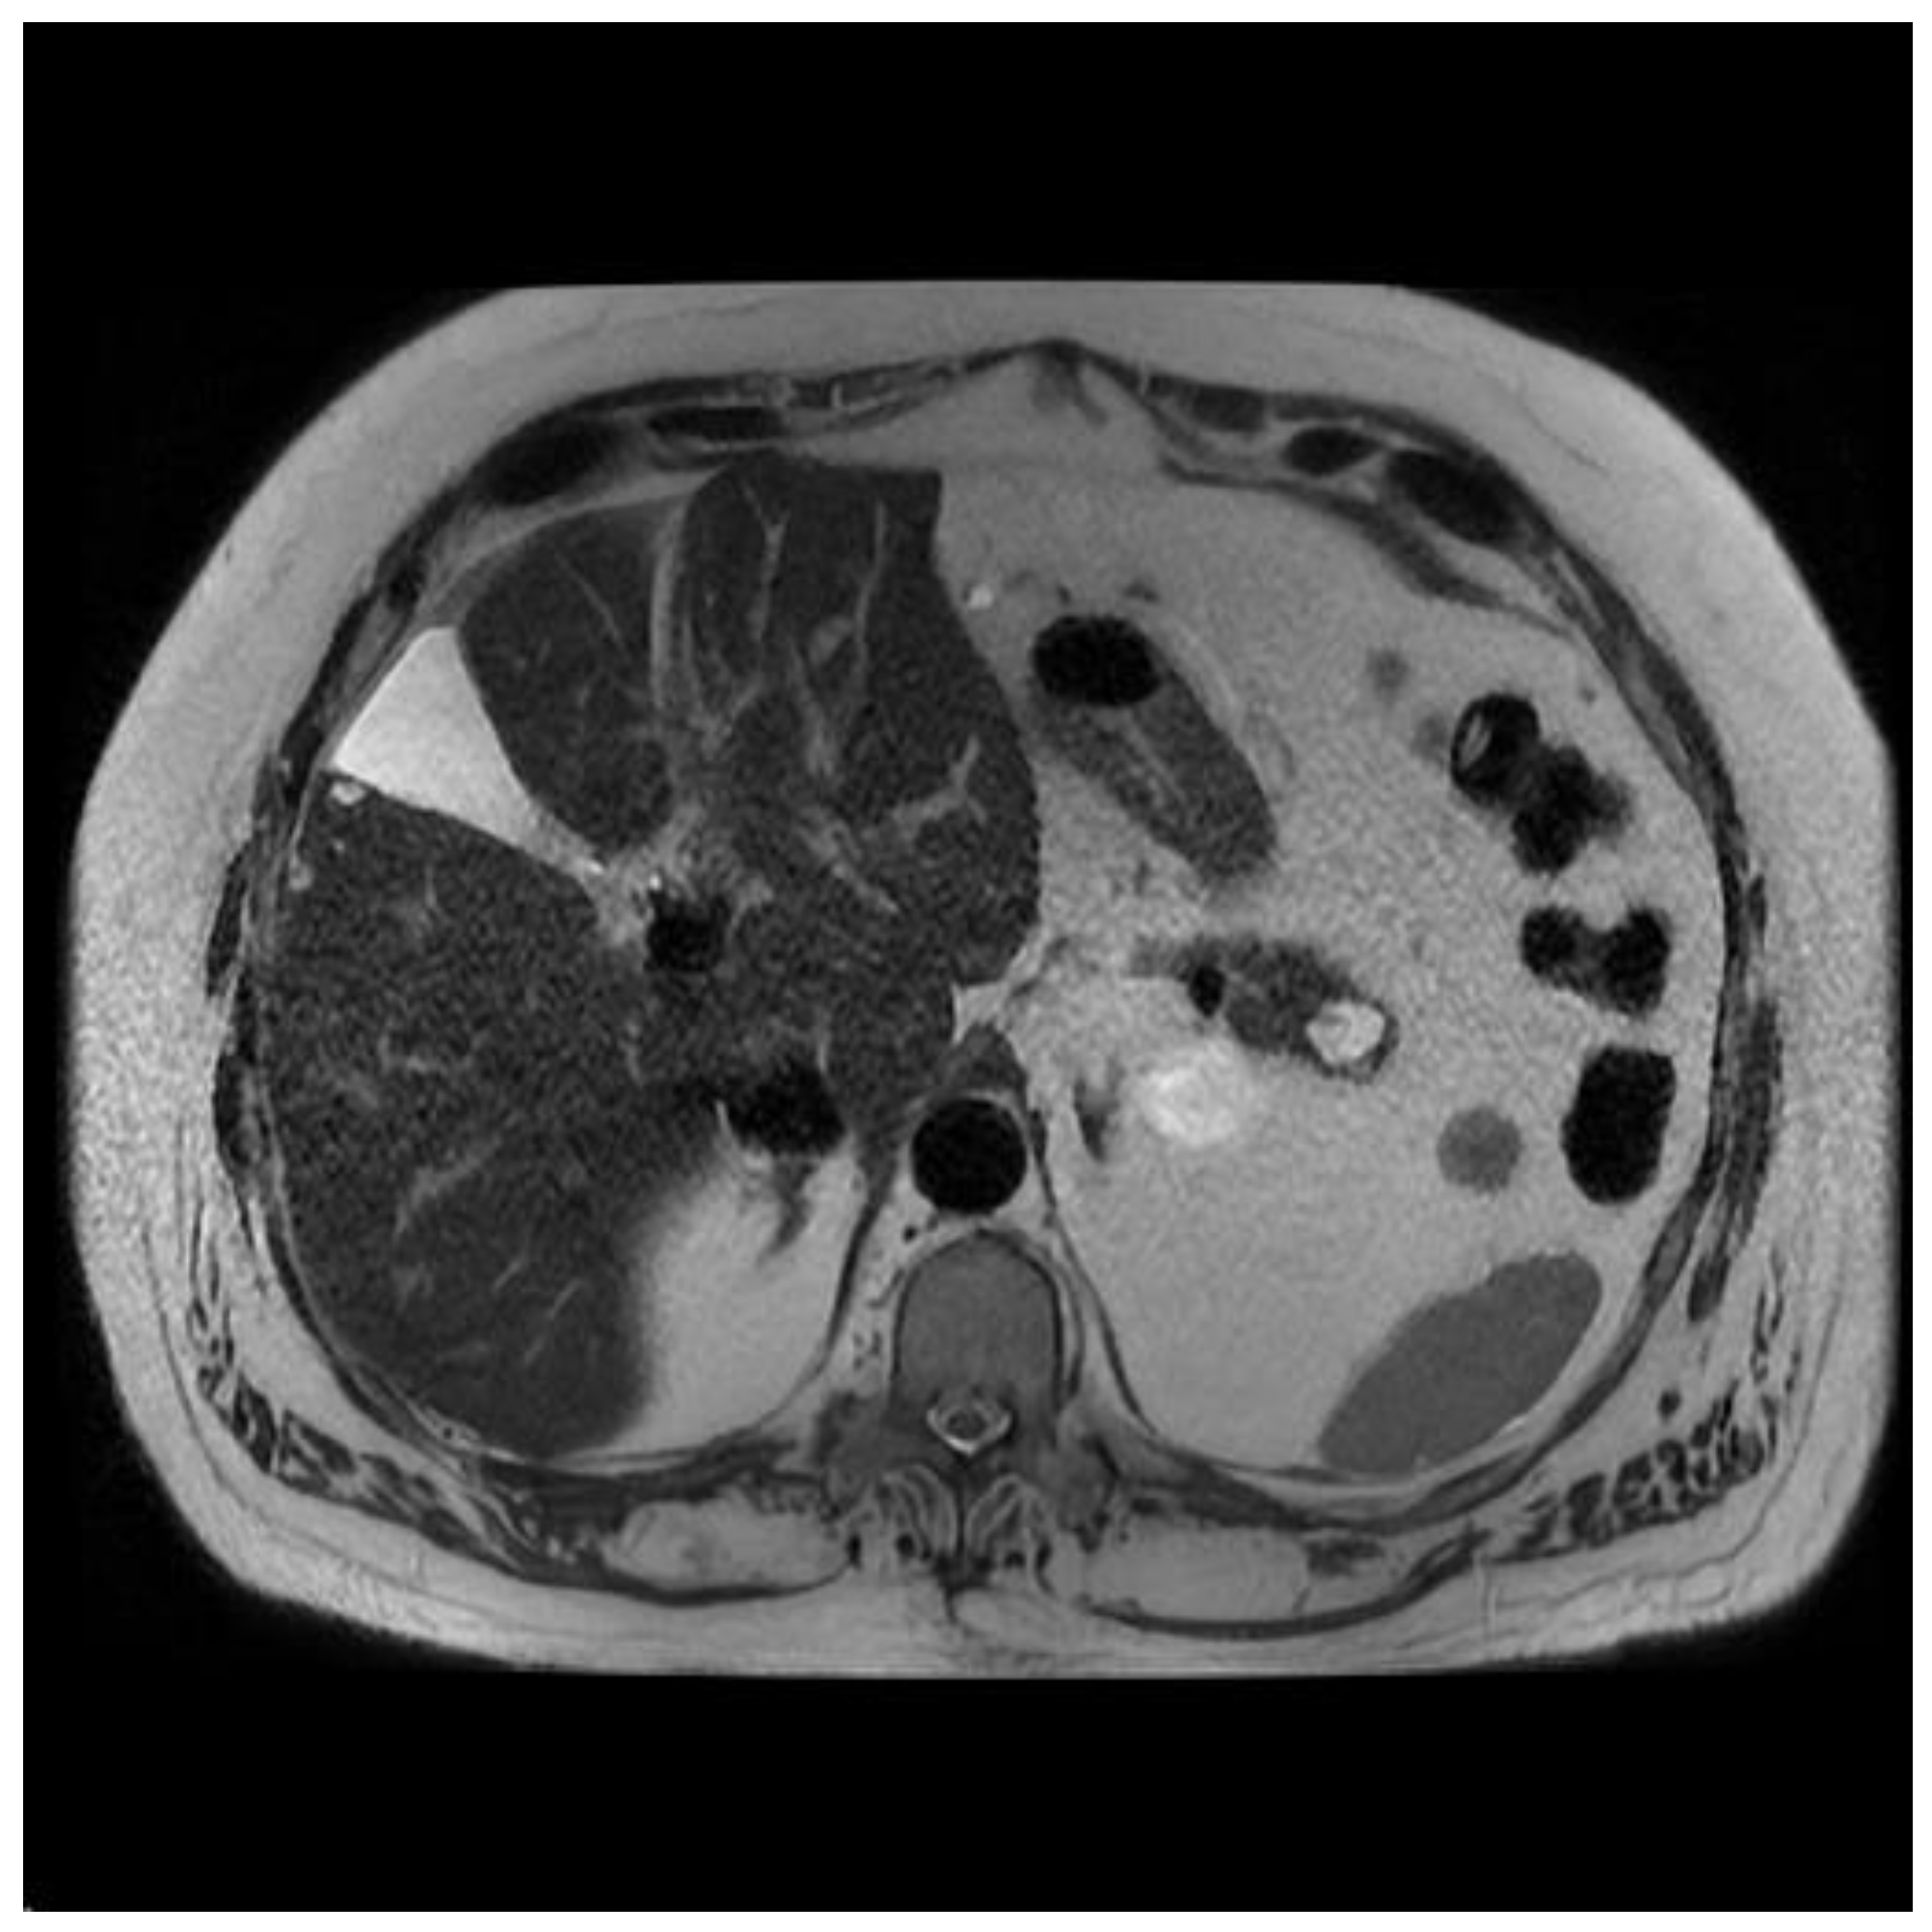

Figure 3.

MRI image of side branch IPMN.